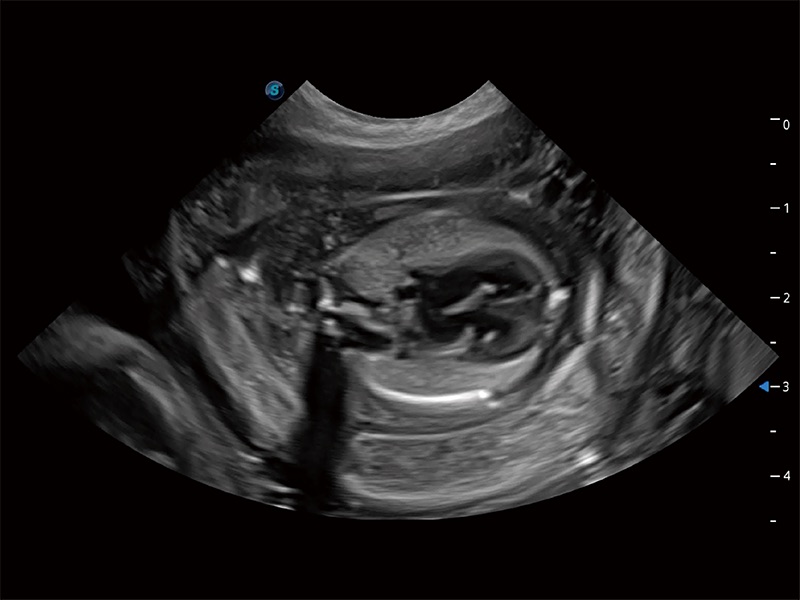

动物是人类最亲密的朋友和最值得信赖的伙伴。球速体育入口也一直致力于探索动物专用的超声影像解决方案。全新推出的ProPet系列,是球速体育入口在动物超声影像智能化、专业化、精准化的一次跨越式革新。动物不能用言语来表述自己的不适,通过超声影像,ProPet系列搭建了动物医生与不同物种沟通的“桥梁”,为动物医生注入了“治愈之力”。 ProPet 80 是球速体育入口匠心打造的一款高端动物专用彩超,采用性能卓越的全新硬件架构,极大提升超声系统的运行效率和数据处理能力,帮助动物医生从容应对日益增多的挑战性病例和日益多样化的临床需求。

高性能和先进的临床应用工具可以为动物医生提供临床信心。ProPet 80 搭载了先进的腹部和浅表应用工具,帮助医生在日常临床实践中发挥前所未有的作用。

ProPet 80 专为动物医生设计,对不同的动物体型和生理结构作出了针对性的优化。通过动物影像专用软件,可满足个性化的应用需求,帮助动物医生获得更精确的诊断数据。

ProPet 80 全新的动物超声智能软件和丰富的探头群,为动物医生提供了高清晰度和精细分辨率的图像,无论在宠物、马科、畜牧还是实验室动物等应用中都可以轻松应对,为您的日常工作带来满意的体验。